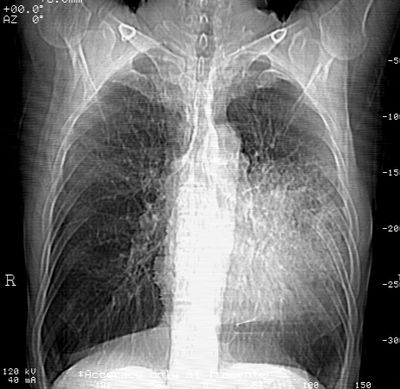

标题: CT24000:M65,胸痛,胸闷月余,既往慢支,肺气肿,肺心病 [打印本页]

标题: CT24000:M65,胸痛,胸闷月余,既往慢支,肺气肿,肺心病

左肺门肿块,相应支气管闭塞,左肺上叶、舌叶大片及散在高密度影,部分呈不张改变,两肺纹粗乱,左侧胸腔积液。考虑左侧中央型肺癌伴阻塞性改变。

左肺门见巨大软组织肿块影,直径约--,境界清,左上肺叶支气管变窄,左上肺舌叶见大片状密实影,余肺纹理增多、紊乱、纤细、部分网格状,两肺透亮度增高,纵隔内见增大多发淋巴结影,心影略左偏,左侧少量胸腔积液。

左侧中央型肺癌伴左上肺舌叶不张、纵隔淋巴结转移,左侧少量胸腔积液。